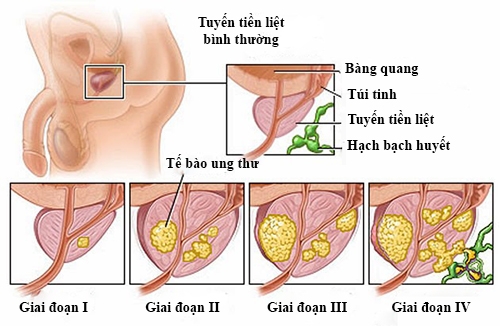

Ung thư tiền liệt tuyến: Triệu chứng và các cách điều trị

Ung thư tiền liệt tuyến thường gặp ở nam giới. Nắm được các triệu chứng bệnh, từ đó thăm khám sớm sẽ tăng hiệu quả điều trị bệnh ung thư tiền liệt tuyến.

Dấu hiệu nhận biết ung thư tuyến tiền liệt

Ung thư tuyến tiền liệt là gì? Dấu hiệu nhận biết ung thư tuyến tiền liệt? Bệnh này có nguy hiểm không? Bài viết này sẽ thông tin đến bạn: